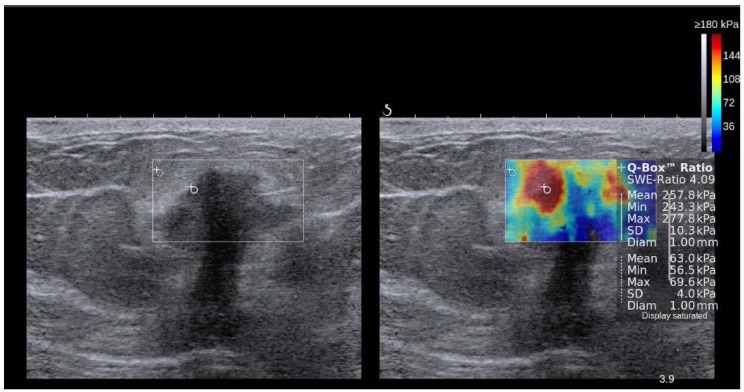

در SWI، یک اندازه گیری کمی از سرعت موج برشی (m/sec) یا مدول یانگ (kPa) در یک ضایعه یا به عنوان یک مقدار واحد در یک ناحیه کوچک ثابت مورد علاقه (ROI) یا برای هر پیکسل در یک میدان به دست می آید. کادر نمای (FOV) به صورت نقشه رنگی 19، 67 نمایش داده میشود. معمولاً از مقیاس رنگی از 0 (آبی تیره = نرم) تا 180 کیلو پاسکال (قرمز = سخت) در سینه USE 73 استفاده میشود (شکل 7).

نمایش کنار هم از تصویر آناتومیک B-mode ایالات متحده (سمت چپ) و نقشه رنگی روکش شده از اندازه گیری امواج برشی همزمان (سمت راست) یک ضایعه پستان که با 2D-SWE در SuperSonic Imagine (SSI) AixplorerTM به دست آمده است. در این سیستم رنگ قرمز نشان دهنده بافت سفت و رنگ آبی نشان دهنده بافت نرم است. ضایعه هیپواکوئیک مشکوک (در داخل مستطیل در تصویر حالت B نشان داده شده است) دارای حاشیه نامنظم، حاشیه های زاویه ای، کمی پهن تر از ارتفاع است و سایه های آکوستیک خلفی را نشان می دهد. الاستوگرام اتیولوژی بدخیم را به دلیل افزایش سفتی (قرمز/زرد/سبز) پیشنهاد کرد و آدنوکارسینوم مجرای در بیوپسی بعدی تایید شد. تصویر توسط دکتر اسمار سایتو.